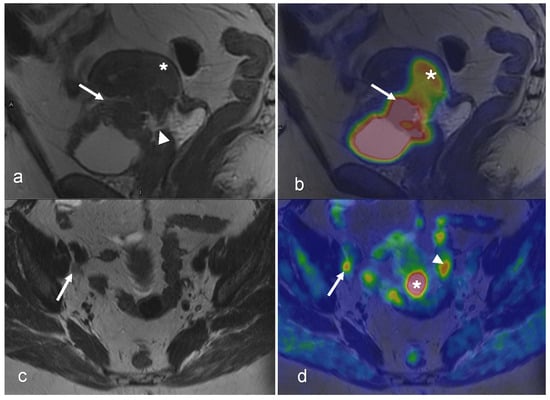

3.1. Cervical Cancer